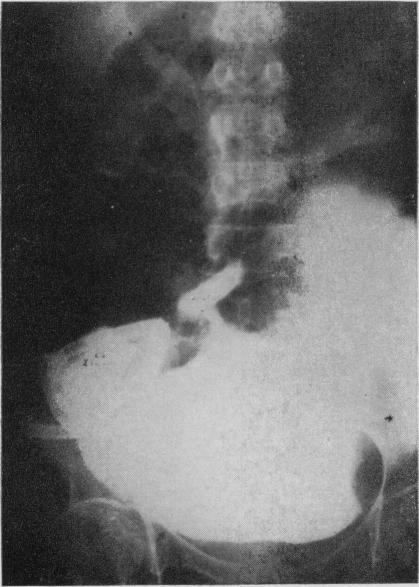

Sigmoid segment substitutes for bladder.